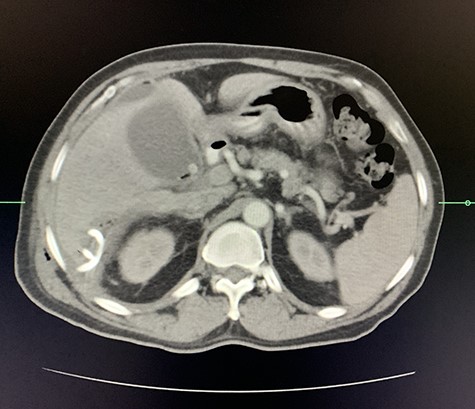

A size 12 French percutaneous catheter was inserted into the large liver abscess. The purulent material drained tested negative for organisms, amoebic and hydatid disease (Fig. 4). A sinogram was performed by injecting contrast through the catheter, showing passage into the ascending colon, confirming the initial diagnosis (Fig. 5).

Axial view of arterial phase of CT scan of the abdomen cholecystitis with pneumobilia with resolving liver abscesses with percutaneous pigtail catheter in situ.